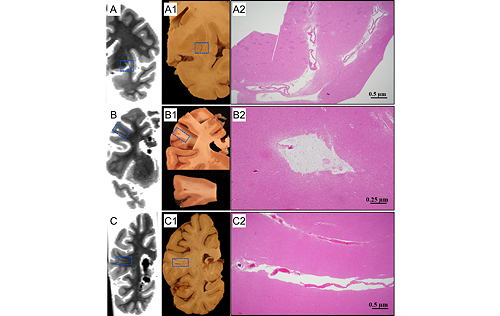

- We have histologically confirmed cerebral microbleeds detected ex-vivo.

- We have histologically confirmed enlarged perivascular spaces detected ex-vivo.

- Nag S, Chen EY, Johnson R, Tamhane A, Arfanakis K, Schneider JA. Ex vivo MRI facilitates localization of cerebral microbleeds of different ages during neuropathology assessment. Free Neuropathol 2021;2:35.

- Javierre-Petit C, Schneider JA, Kapasi A, Makkinejad N, Tamhane AA, Leurgans SE, Mehta RI, Barnes LL, Bennett DA, Arfanakis K. Neuropathologic and Cognitive Correlates of Enlarged Perivascular Spaces in a Community-Based Cohort of Older Adults. Stroke 2020;51:2825-2833.